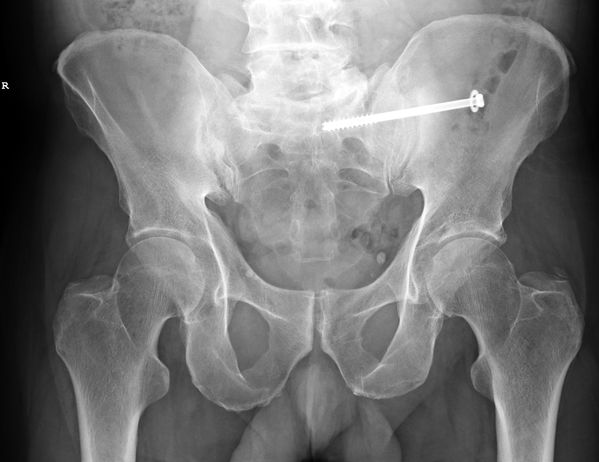

The company Synthes Costa Rica S.C.R. Ltda provides elastic titanium nails and osteosynthesis systems to 24 hospitals in this Central American country through a contract with the Caja Costarricense de Seguro Social (CCSS). The company’s current contract will finish in September and many were surprised to hear that it was recently renewed despite a fraud investigation.

Reports confirm that the CCSS will continue to purchase nails from this company until April 4th, 2015 under one contract worth $57,600 and the osteosynthesis systems until June 15th, 2015 under a second contract for $448.500.